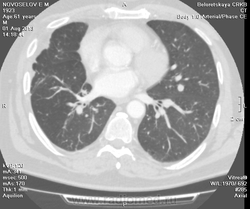

Мужчина оперирован по поводу BL щитовидной железы.Неоднократно проходил КТ в других лечебных учреждениях, у нас- впервые.Ставились заключения:MTS в лёгкие и лимф.узлы средостения слева.Образование слева увеличилось.Жалуется на одышку, не верит в заключение о MTS,просит узнать мнение других специалистов.

Метастазов в легкие не вижу. Похоже на лимфоузел в головке левого корня. Если позволите, запаздываете с началом исследования, плотность контраста в легочных артериях должна быть выше, чем а аорте. А одышка, не мудрено, легочная ткань диффузно уплотнена по типу "матового стекла", написал бы какую-нибудь интестициальную пневмонию, по типу альвеолита, может быть и гиперчуствительный пневмонит (не разберу есть или нет внутридольковые очажки), посмотреть бы изначально легочное окно, а не восстановленное из мягкотканного.

В диф. ряд: саркоидоз, атипичная форма.

Кажется,я понял,что Вы имели ввиду.Очажки стрелочкой указал.Согласен с тем,что очаги на фоне отображеничя сосудов кажутся фантазией,но они присутствуют.

Коллега, вынужден извинться и дезавуировать свой первый пост. Пересмотрел. Да, есть очаги, и они - вероятнее всего, метастазы.

Единственное,что напрягает,так это то,что эти изменения у пациента более 1,5 лет.А вид внешний у него не так уж и плох.А слева это всё-таки лимфоузел, а не периферическое образование в S3?

Думаю, да. Слишком близко лежит к легочной артерии.